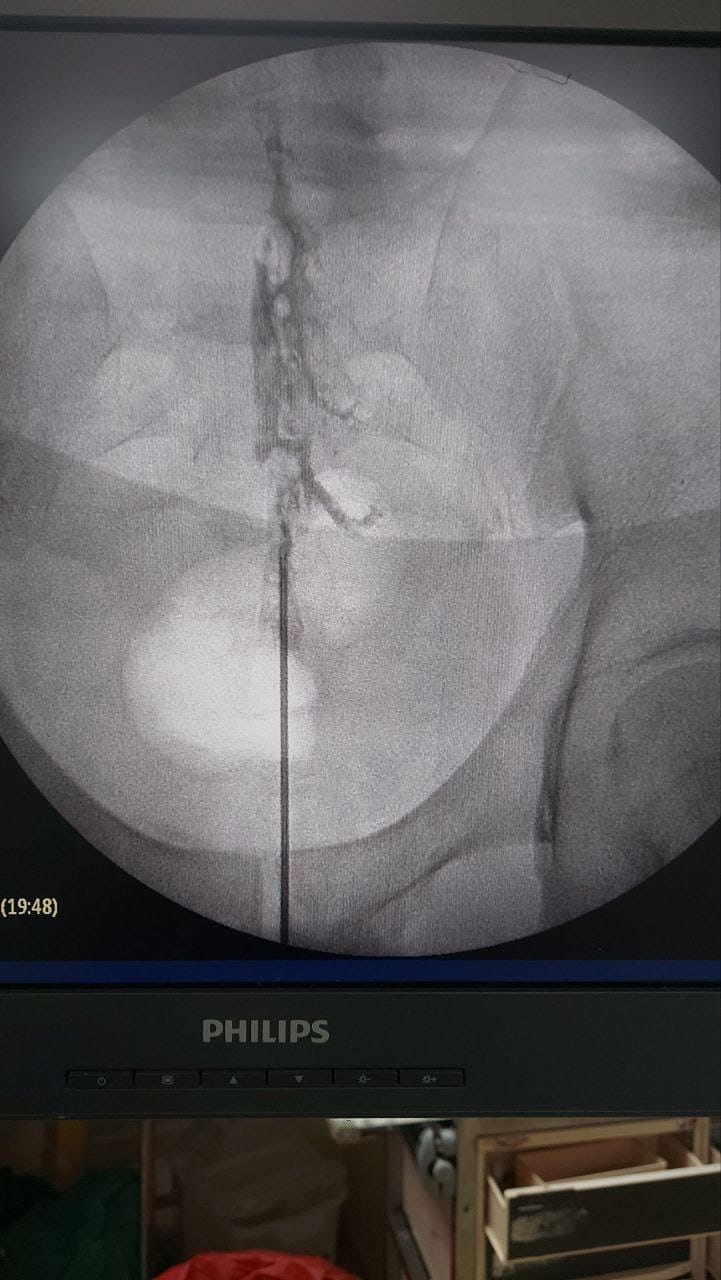

Procedures